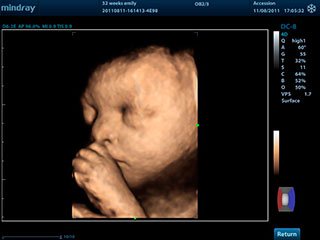

3D/4D УЗИ при беременности

4D УЗИ дает возможность разглядеть мельчайшие детали строения, например, пол ребенка, количество пальчиков на ручках и ножках. Если проводить 4 d диагностику на 32 неделе беременности, то можно увидеть мимику ребенка, как он улыбается или хмурится.